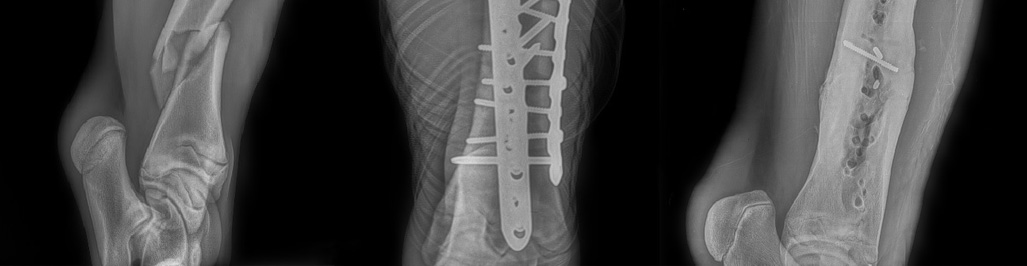

Major Fracture

State-of-the-art locking compression bone plate technology

We use only Synthes-DePuy orthopedic implants

- Breakdown injury

- Arthrodesis (joint fusion)